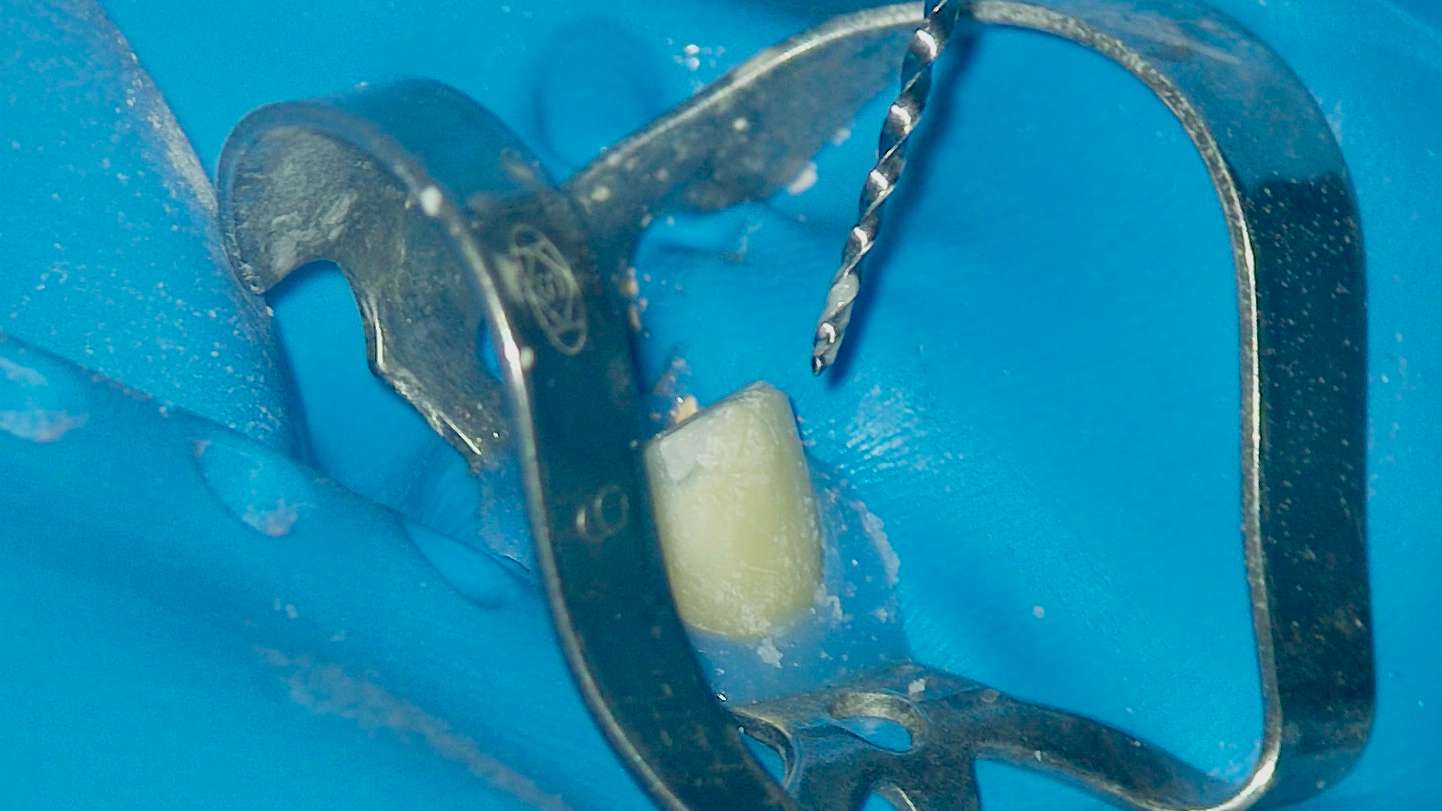

Обтурация биокерамическим силером с гуттаперчей. Автор: Диана Кипарисова